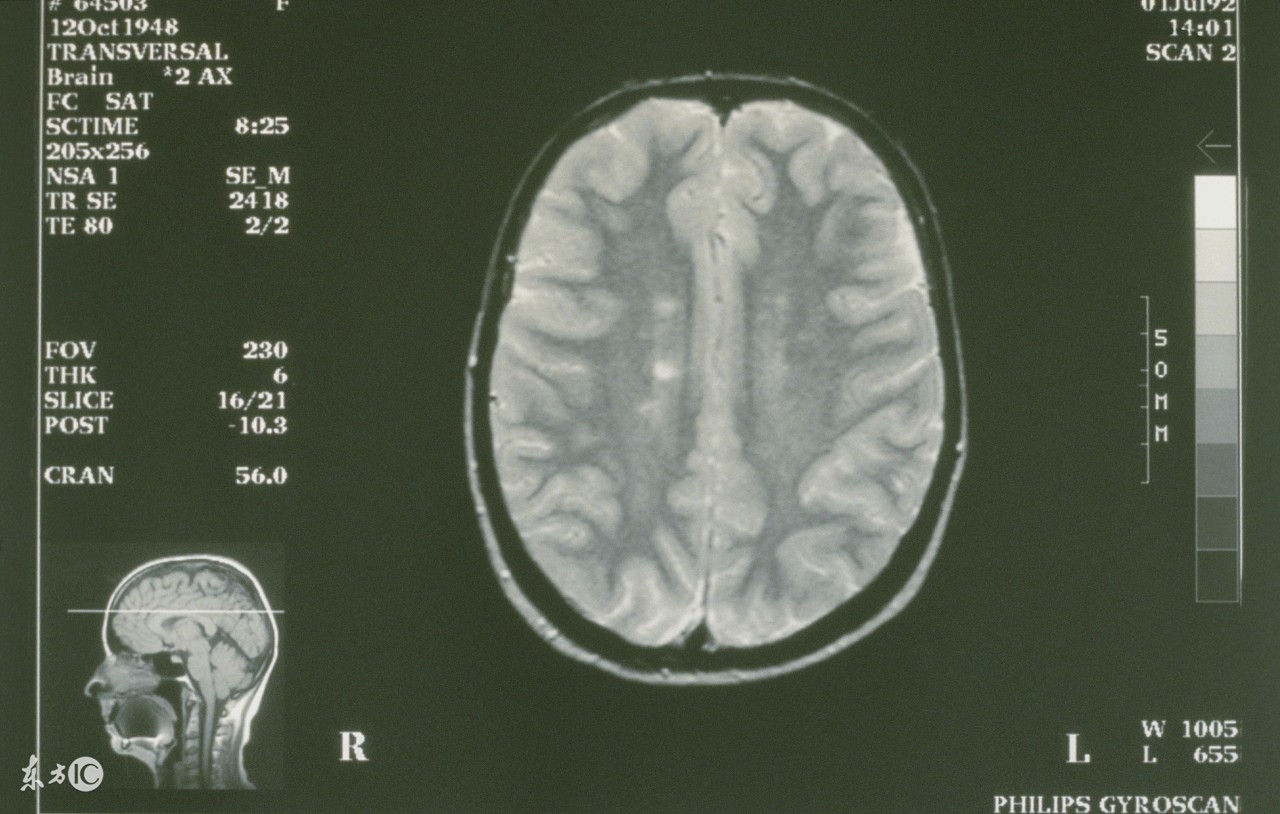

病理性手抖,医学上称为“震颤”,是指手不随意地颤动,常为永久性的,其病根可能是由于某种疾患使大脑涉及运动协调功能的区域受到损害。

4、小脑病变。小脑参与躯体平衡和肌肉张力的调节,以及随意运动的协调,一旦小脑发生病变,患者会出现意向性震颤,即患者越接近目标物体,其抖动越明显。此外,还可出现眼球震颤、言语改变以及站立行走不稳等共济失调的表现。